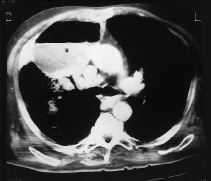

Un varónde 69 años con historia de hipertensión arterial yenfermedad pulmonar obstructiva crónica (EPOC) fue ingresadoen el hospital por agudización de su insuficienciarespiratoria crónica. Dos semanas más tarde,presentó oliguria progresiva, hiperuricemia e hiperkaliemiapor fracaso renal obstructivo secundario a un adenoma depróstata cuyo diagnóstico se desconocía. Porello, fue ingresado en nuestra unidad con cuadro deencefalopatía urémica y fracaso respiratorio,requiriendo intubación endotraqueal y ventilaciónmecánica. La primera radiografía torácica enla UCI mostró ausencia de hallazgos anormales. Tras elsondaje uretral, el fracaso renal se resolvió, y no fueronnecesarios procedimientos dialíticos. A las setenta y doshoras tras el ingreso en UCI, estando el paciente enventilación mecánica, presentó cuadro febrilcon temperatura de 38,5 ºC que se continuó con signosde shock séptico, precisando soporte hemodinámico condopamina y posteriormente noradrenalina. La radiografía detórax mostró un infiltrado en el lóbulosuperior derecho. En el aspirado traqueal se cultivóAcinetobacter baumannii (>106 ufc/ml),modificándose el tratamiento a imipenem y amicacina. En laradiografía se hizo evidente una progresión hacia lacavitación en el lóbulo pulmonar superior derecho. Latomografía axial computarizada (TAC) torácica (fig.1)mostró una gran colección líquida con gas anivel superior en el segmento anterior de dicho lóbulo, conconsolidación alveolar periférica por infiltradoneumónico. Las muestras recogidas por broncoscopia pusieronde manifiesto de nuevo el crecimiento significativo deAcinetobacter baumannii, no observándosecélulas neoplásicas, siendo el resultado negativopara la tinción de Zielh-Nielsen y el cultivo en medioLowenstein. Se procedió a drenaje percutáneo de lacavidad, con mejoría parcial del paciente, y el cultivo desu contenido confirmó Acinetobacter baumannii con lamisma sensibilidad a antimicrobianos que en las pruebas anteriores.No se cultivaron microorganismos anaerobios en el material delabsceso.

Fig. 1. Tomografía axial computarizada (TAC) detórax realizado a los diecinueve días de estancia enla unidad de cuidados intensivos (UCI) mostrando una grancolección líquida en el lóbulo pulmonarsuperior derecho con infiltrado neumónicoperiférico.